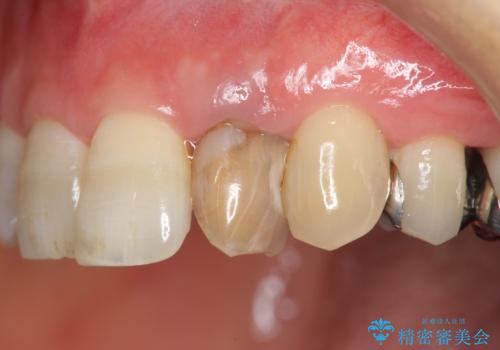

- 目立つ前歯の著しい変色の改善を求めて来院されました。

根管治療が為されたまま、クラウンの装着が行われず変色し審美障害を来している状態です。

維持を保つためのファイバーコア築盛を行い、精密なジルコニアクラウン製作を行います。